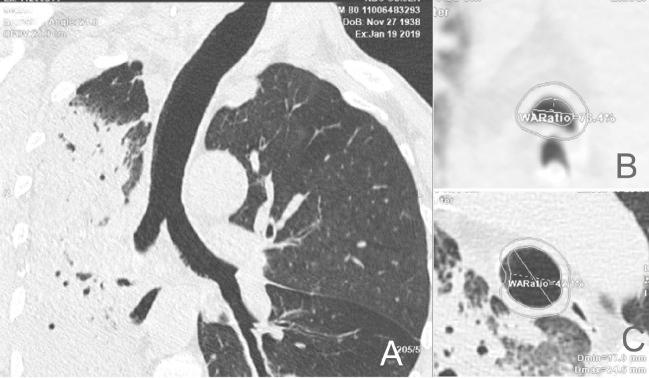

Tracheal measurements in the intensive care unit (ICU) are important for the choice of endotracheal tube and may correlate with patient demographic characteristics and infections. The study included 42 surgical patients, age 60 [48-71] years, who underwent diagnostic chest computed tomography (CT) scans during treatment in the ICU, Osijek University Hospital, in 2019 and 2020. CT scans were analyzed using AW Server 3.2. Measurement analysis showed that the diameters of the tracheobronchial tree, the length of the trachea and left main bronchus were significantly larger in men compared to women (p<0.05 all). The smallest tracheal upper diameter was 15.25 [IQR 11.8-18.8] mm vs. 17.95 [13.55-20.05] mm in septic and nonseptic patients, respectively (p=0.028). A total of 26 patients who underwent CT scans developed nosocomial pneumonia. It was right-sided in 15, left-sided in 6 and bilateral in 5 patients, and correlated significantly with the left main bronchus length (ρ=0.515, p=0.007). No correlation was observed between tracheobronchial measurements and length of ICU treatment, number of hours spent on mechanical ventilation, or survival. A larger study could provide better data on the importance of tracheobronchial tree measurements in ICU patients.

重症监护病房(ICU)的气管测量对于选择气管内管非常重要,并且可能与患者的人口统计学特征和感染有关。本研究纳入了 2019 年至 2020 年期间在奥西耶克大学医院 ICU 接受治疗的 42 名外科患者,年龄 60 [48-71] 岁,他们接受了诊断性胸部计算机断层扫描(CT)检查。使用 AW Server 3.2 分析 CT 扫描。测量分析表明,与女性相比,男性的气管支气管树直径、气管和左主支气管长度明显更大(p<0.05 均)。发生脓毒症和非脓毒症的患者,气管上段最小直径分别为 15.25 [IQR 11.8-18.8] mm 和 17.95 [13.55-20.05] mm(p=0.028)。总共 26 名接受 CT 扫描的患者发生了医院获得性肺炎。右侧 15 例,左侧 6 例,双侧 5 例,与左主支气管长度显著相关(ρ=0.515,p=0.007)。气管支气管测量与 ICU 治疗时间、机械通气时间或生存率之间无相关性。更大的研究可以提供 ICU 患者气管支气管树测量重要性的更好数据。